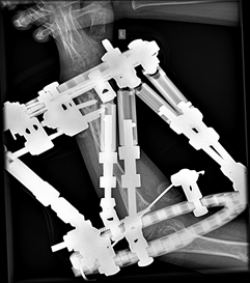

The images show a case of Olier’s disease which had a short and deformed forearm. He underwent surgical intervention by Dr. Zenios with the use of external osteosynthesis.

External osteosynthesis